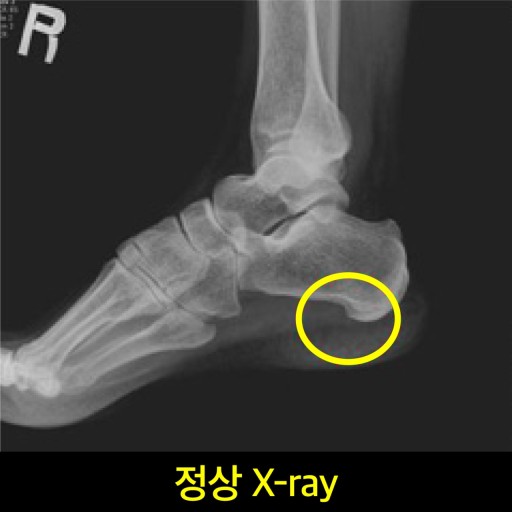

1. 족저근막염 (Plantar Fasciitis)

📌 증상:

- 아침에 일어나 첫발을 디딜 때 발뒤꿈치와 발바닥에 극심한 통증

- 오래 앉아 있다가 일어설 때 통증이 심해지고 움직이면 점차 완화

📌 원인:

족저근막은 발뒤꿈치뼈(종골)에서 시작해 발가락까지 이어지는 강한 섬유 조직인데, 장시간 서 있거나 무리한 운동을 하면 이 조직이 미세하게 찢어지면서 염증이 생깁니다.📌 위험 요인: